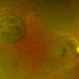

- Optical coherence tomography system

- Optical coherence tomography image over a CHRPE lesion.